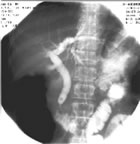

肝内胆管结石的诊断对于单纯胆管结石未合并感染或其他合并症者,特别是“静止期”内易误诊为肝

炎、胃病等,应注意鉴别。影像学检查有助于诊断及鉴别诊断。B超、PTC检查可显示肝内胆管结石的分布和肝胆管的狭窄和扩张情况,对确定诊断和指导治疗有重要意义。

PTC 的X线特征有:

①肝总管或左右肝管昝有环形狭窄,狭窄近端胆管扩张,其中可见结石阴影;

②左右肝管或肝内某部分胆管不显影;

③左右叶肝内胆管呈不对称性、局限性、纺锤状或哑铃状扩张。CT也有重要诊断价值,特别是对于并发胆汗性肝硬化和癌变者。